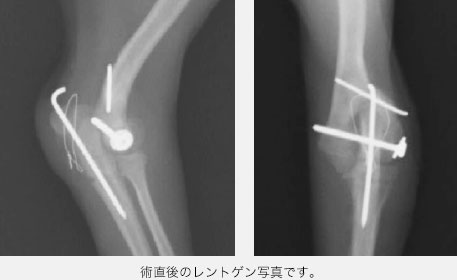

まず肘の上腕骨にアプローチするために、尺骨という骨の一部を切断し、視野を広くしました。

骨折端が見えたところで、横方向にはスクリュー固定(ラグスクリュー法といいます)を行い、縦方向(骨が伸びる方向)にはワイヤーを使った方法を用いました。骨折端がピッタリとくっついているのを確認した後に、先ほど切断した尺骨の切断面を戻しワイヤーにて固定しました。